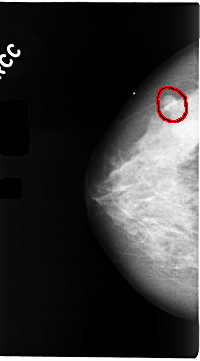

C_0104_1.RIGHT_CC

FILE: C_0104_1.RIGHT_CC.OVERLAY

TOTAL_ABNORMALITIES 1

ABNORMALITY 1

LESION_TYPE MASS SHAPE OVAL MARGINS CIRCUMSCRIBED

ASSESSMENT 3

SUBTLETY 5

PATHOLOGY BENIGN

TOTAL_OUTLINES 1

BOUNDARY